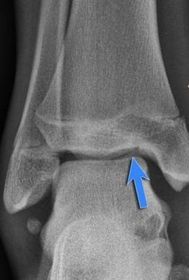

| What is this? | Os subtibiale |